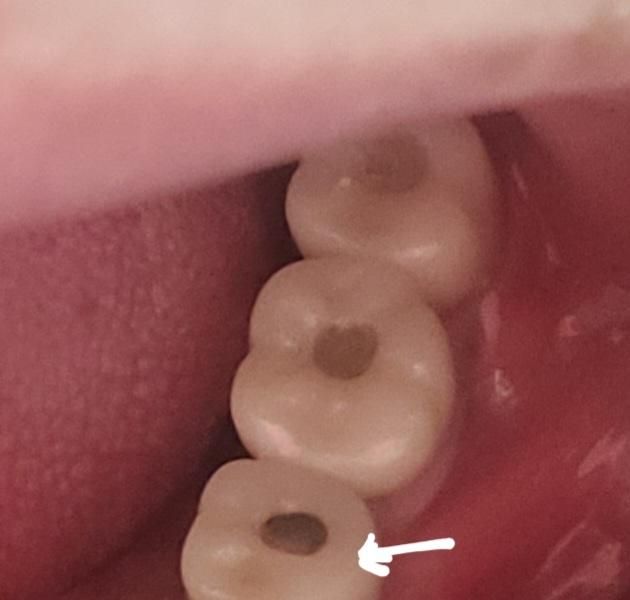

말그데로임플란트크라운에 홀ㅇㅣ있는데그홀매운부분에 레진이 떨어진거 같아요..세개가 붙은건데 한개만 떨어지고 두개는 그데로인거같아요..떨어진한개도완전히 떨어진건아니고 검게 지대주가 살짝 보이는거 같아요..불편한건없는데 가끔 거기에 음식물이 낀다는거요.

임플란트 홀을 레진으로 채우는건 위생사 선생님이 하셔도 되는 업무 입니다. 비보험이라 치과마다 다르지만 대략 5만원정도 비용을 받습니다.

임시재료를 충전하는것이 아닌 레진을 충전하는것은 치과의사가 해야 합니다. 비용은 임플란트 관리차원에서 해주는경우도 있고 추가적인 비용이 나가는 경우도 있습니다.